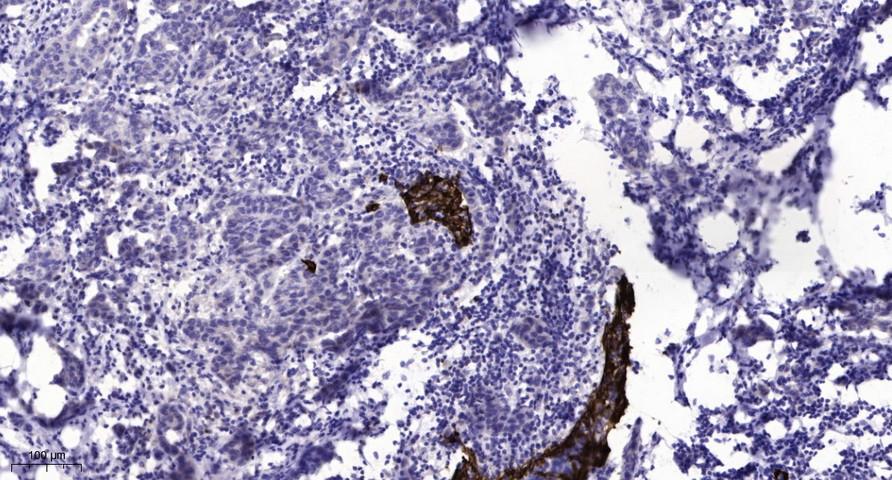

Immunohistochemical analysis of paraffin-embedded human Breast cancer. 1, Antibody was diluted at 1:200(4° overnight). 2, Tris-EDTA,pH9.0 was used for antigen retrieval. 3,Secondary antibody was diluted at 1:200(room temperature, 45min).